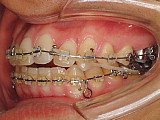

| まず上下の奥歯をゆっくりと後方に移動していきます。 |

奥歯の位置を調整しながら前歯にも装置を付けていきます。

歯列内にスペースができています。 |